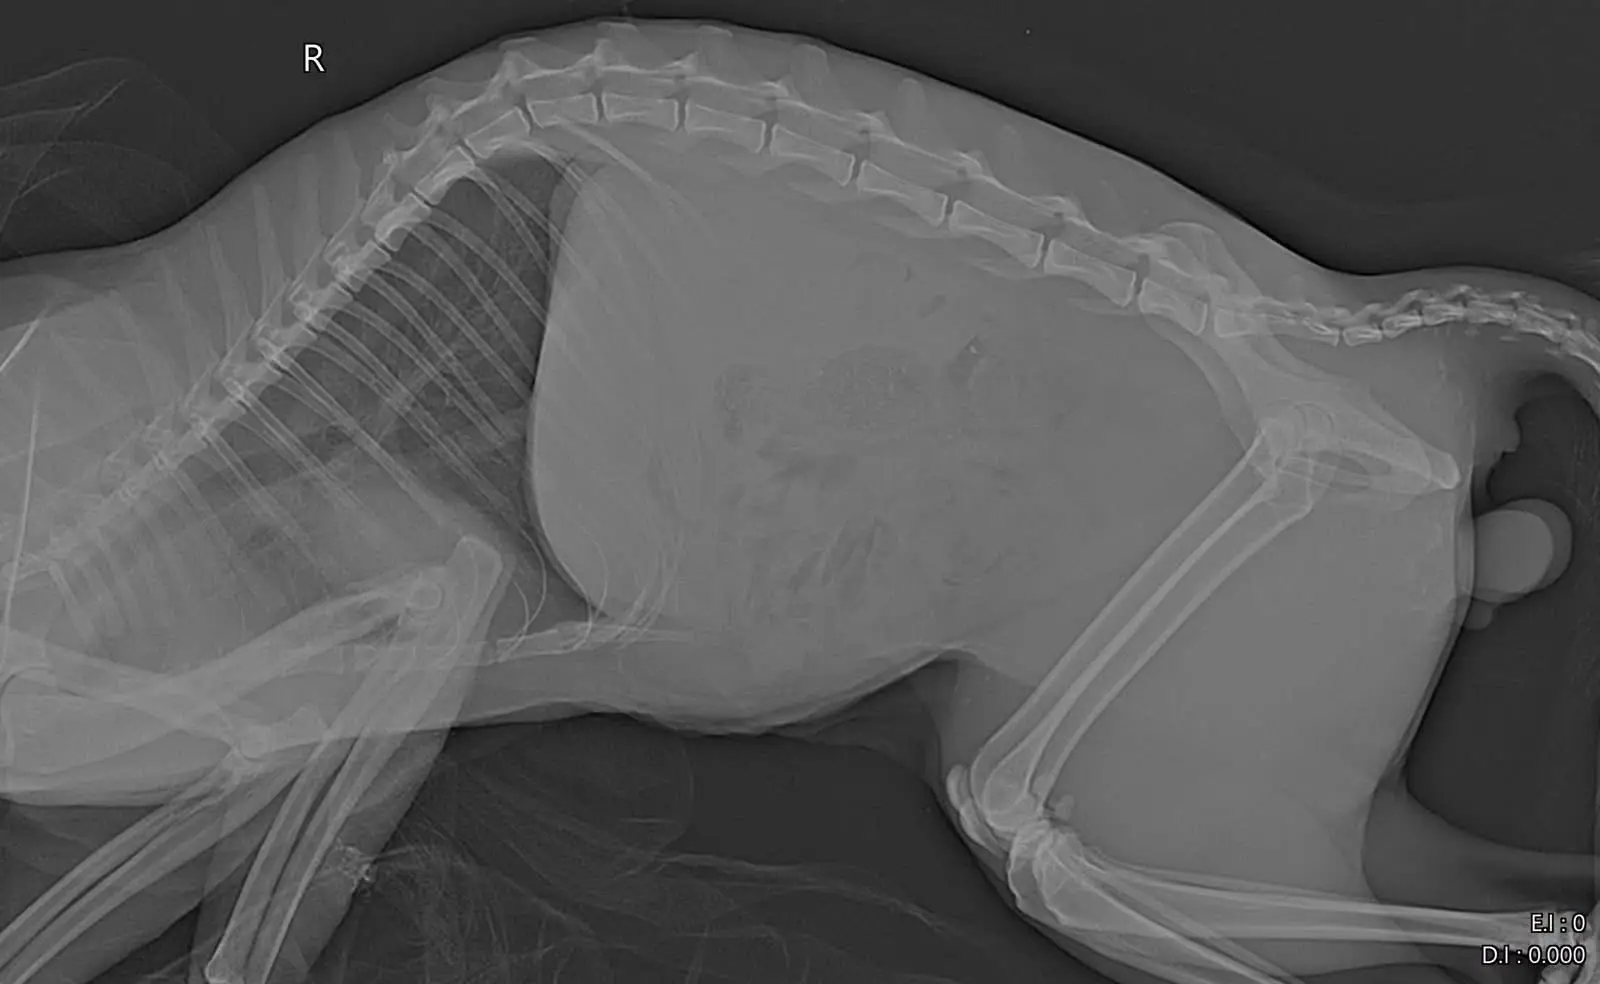

Намерихме Илиян в района на Кючук Париж в безпомощно състояние. Настанихме го в клиника „Провет“ веднага.

🏥 СЪСТОЯНИЕТО НА ИЛИЯН

Илиян е пострадал тежко и болката му е огромна. Изследванията показаха:

Счупване на таза

Дислокация (изкълчване), която изисква спешна намеса. За да може това мило създание отново да ходи нормално, е необходима ортопедична операция.